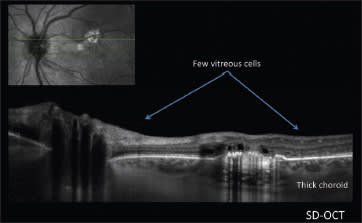

The second multimodal case was of a 52-year-old woman with an acquired vitelliform lesion in the left eye. Autofluorescence shows that the area was hyperautofluorescent, suggesting its origin in the photoreceptors. OCT showed a markedly thickened choroid in both eyes, leading to a diagnosis of an acquired vitelliform lesion related to chronic neurosensory detachment in a case of central serous chorioretinopathy (CSC).